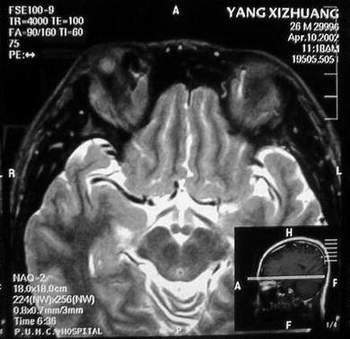

MRI及增强结果如下:

患者压颈及其它Valsava试验结果阴性。从MRI分析,在T1、T2、T+C检查该支血管均为明显流空现象,说明该血管血流速度很快,而从走行和分布看,眼上静脉可能性很大。也许也不能除外异常的眼动脉或异常血管。眶内主要可能的血管病变包括颈内动脉海绵窦瘘(高流窦)、AVM、眼眶静脉曲张、海绵状血管瘤、静脉性血管瘤、毛细血管瘤和眶内动脉瘤。。 1、颈内动脉海绵窦瘘:该患者临床有一部分支持该诊断。但从影像分析,海绵窦未见明显扩张;眼外肌未见明显充血扩张的长T1、长T2信号;颈内动脉海绵窦瘘常可见继发到血栓,可见到短T1、长T2的血栓信号。 2、眼眶静脉曲张:该疾患一般常见于小儿。该患大多数会出现Valsava试验阳性,间歇性突眼。不符合该患。影像学检查,于曲张静脉内常可见血栓和静脉石。所以不符合该患。 3、AVM:患者目前的影像学资料尚不全面,但可符合该诊断。临床上改病常见于30岁左右年轻人,单侧发病,于本患较符合。问题在于临床没有明确的血管杂音,似乎难以解释。 4、该患影像学与海绵状血管瘤差别很大,所以可基本排除此诊断。 5、静脉性血管瘤和毛细血管瘤:MRI中等T1、长T2信号,较易与本病鉴别。 6、眶内动脉瘤:我觉得患者并不能排除本病,但同样,由于波动性阴性,似乎也难以解释。 纵上所述:本人觉得,患者AVM可能性较大,同时不能除外眶内动脉瘤。 关于进一步检查,我觉得DSA价格过于昂贵。是否可先进行彩色多普勒检查,首先可以明确是静脉系统还是动静脉瘘抑或是动脉瘤。第二步,可进行MRA检查,可以清楚地显示海绵窦地相关关系,并可借此诊断或排除颈内动脉海绵窦瘘。如还需第三部检查,可进行MRV检查,对静脉系统进一步评价。三种检查总共的费用2000多圆,但给予我们的信息量已经很丰富了。 敬请各位医师提出自己的见解。 谢谢!